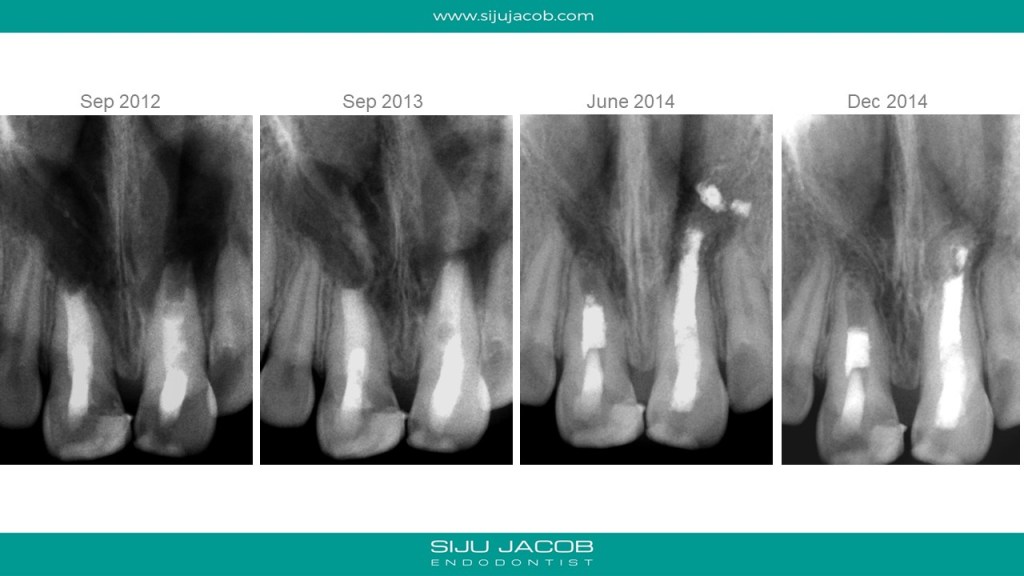

This was probably the largest lesion I ever treated. It had several interesting characteristics. It would be tough to explain with just pics. So, I made it into a short presentation